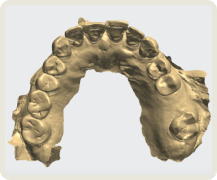

치아 제작시 국내 최고 수준의 장비를 보유한

디지털 치과 전문 기공소와 협업합니다.

개인 맟춤 디지털 수술 가이드

CAD/CAM 지르코니아 크라운